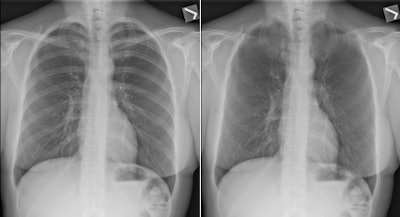

The version 5.7 release includes a bone suppression algorithm that enables radiologists to view thoracic soft tissue without the ribs and clavicles in the way, Foos said. Another feature, designed for visualizing tubes and lines, performs aggressive frequency enhancement but also controls noise boost, while a third algorithm offers texture enhancement designed to help radiologists visualize linear features that might be found in pneumothorax.

The three algorithms can be used in what Carestream calls a companion view mode, in which users can toggle back and forth between enhanced and unenhanced images to better visualize changes, Foos said. The mode uses the initial x-ray exposure and thus does not expose patients to additional radiation.

Carestream provided Saudi officials with examples of images with the processing applied; after that, the MOH ordered 10 more DRX-Revolution systems, in addition to the 15 DRX-Revolution and seven DRX-Evolution systems it recently purchased.